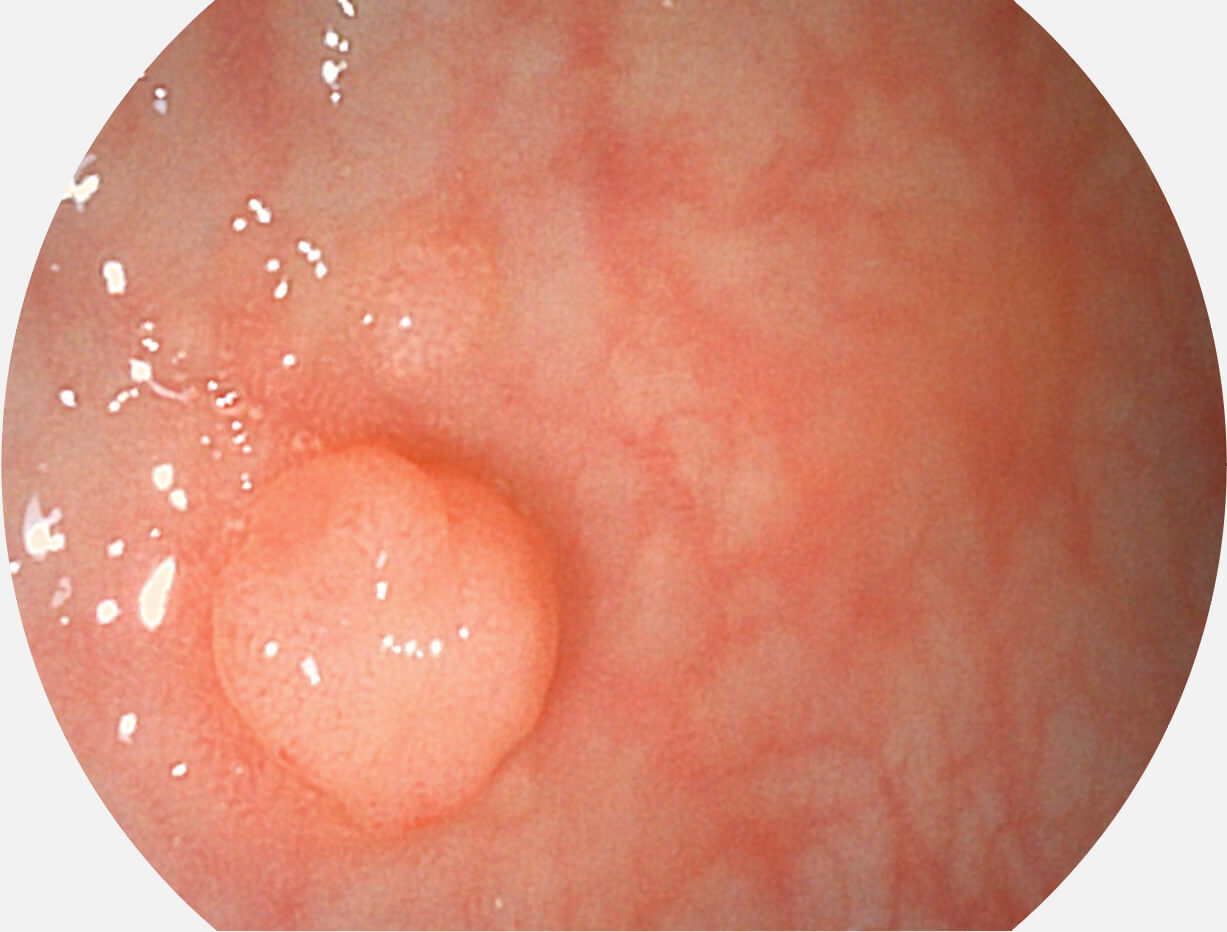

白光图像

SFI图像